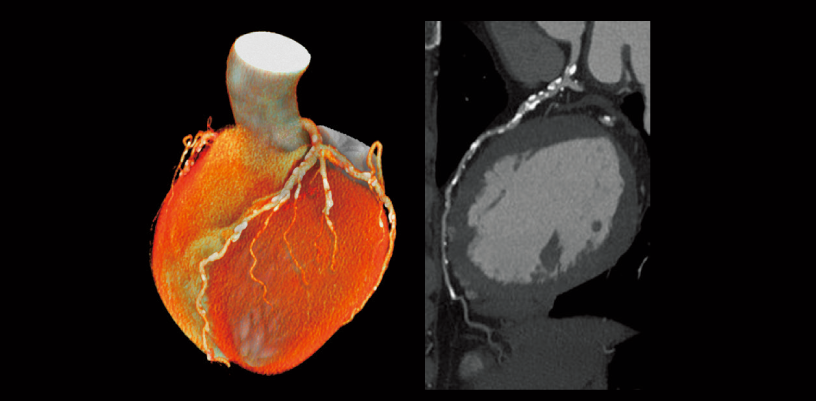

Coronary artery calcifification

Follow-up after CABG

Aortic valve (Cardio StillShot)